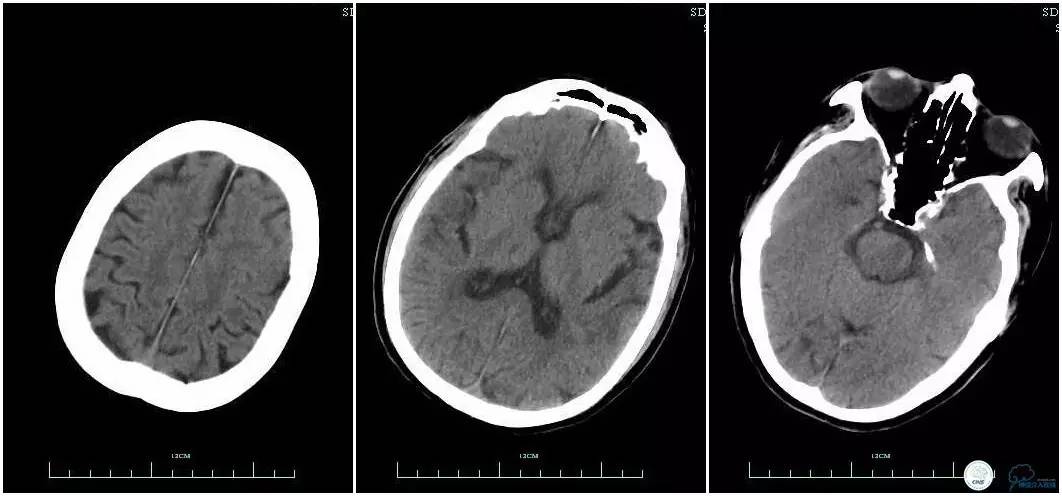

辅助检查:血常规、生化、凝血功能未见明显异常,心电图:窦性心律,ST-T改变;头颅CT平扫:未见明显出血。头颅MRI:未见新鲜梗塞灶;头颅MRA:双侧大脑前动脉远端缺如。

术前头颅CT平扫。

术后头颅CT复查。

术后复查头颅CTA。